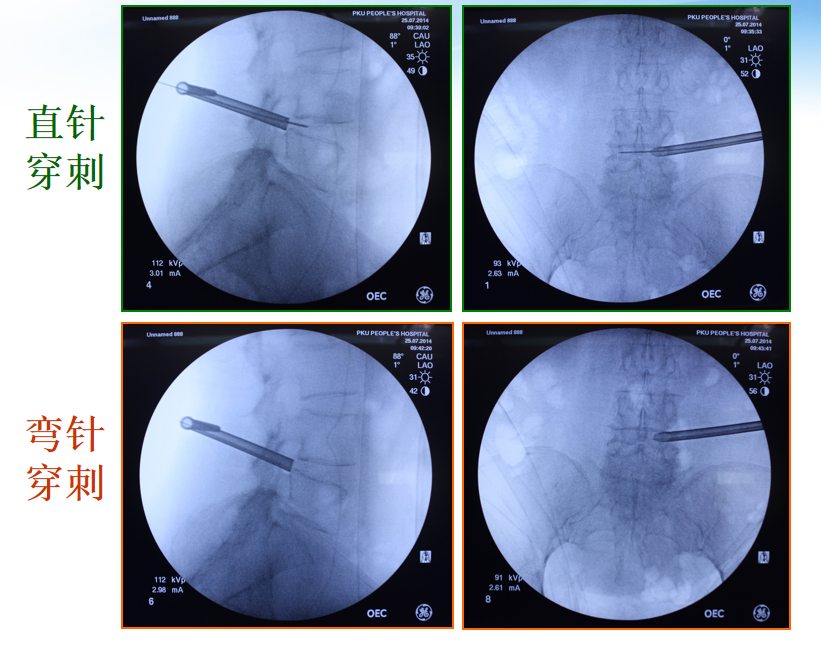

两种穿刺入路的区别

YESS技术(in-out)

• 盘内

• 适应症窄

• 极难处理髂嵴较高和椎间孔狭窄的椎间盘突出

• 技术简单,适合初学医师

TESSYS技术(out-in)

• 椎管内

• 脱出型和游离型腰椎间盘组织, 中央椎管和侧隐窝狭窄等均可有效处理

• 绞除部分上关节突,扩大椎间孔。

• 技术复杂